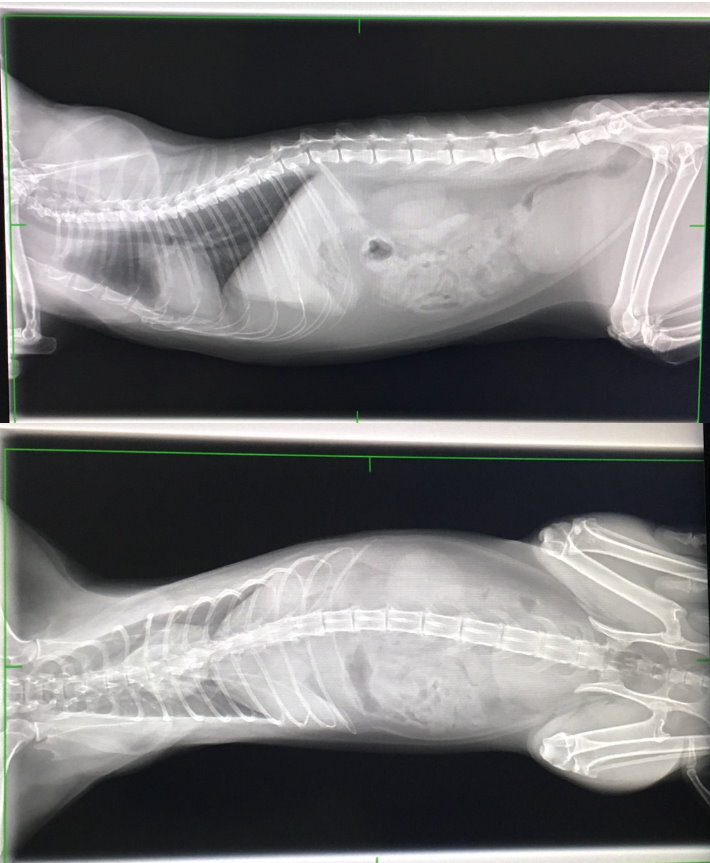

照X光檢查,排除異物阻塞的可能,

卻發現腸道無食物,表示多日未進食

X光中有看到心包膜有些微積水狀況

並於膀胱上發現有一白點,

但做超音波時並未看到結石等異物,

故推測是腸子的疊影。